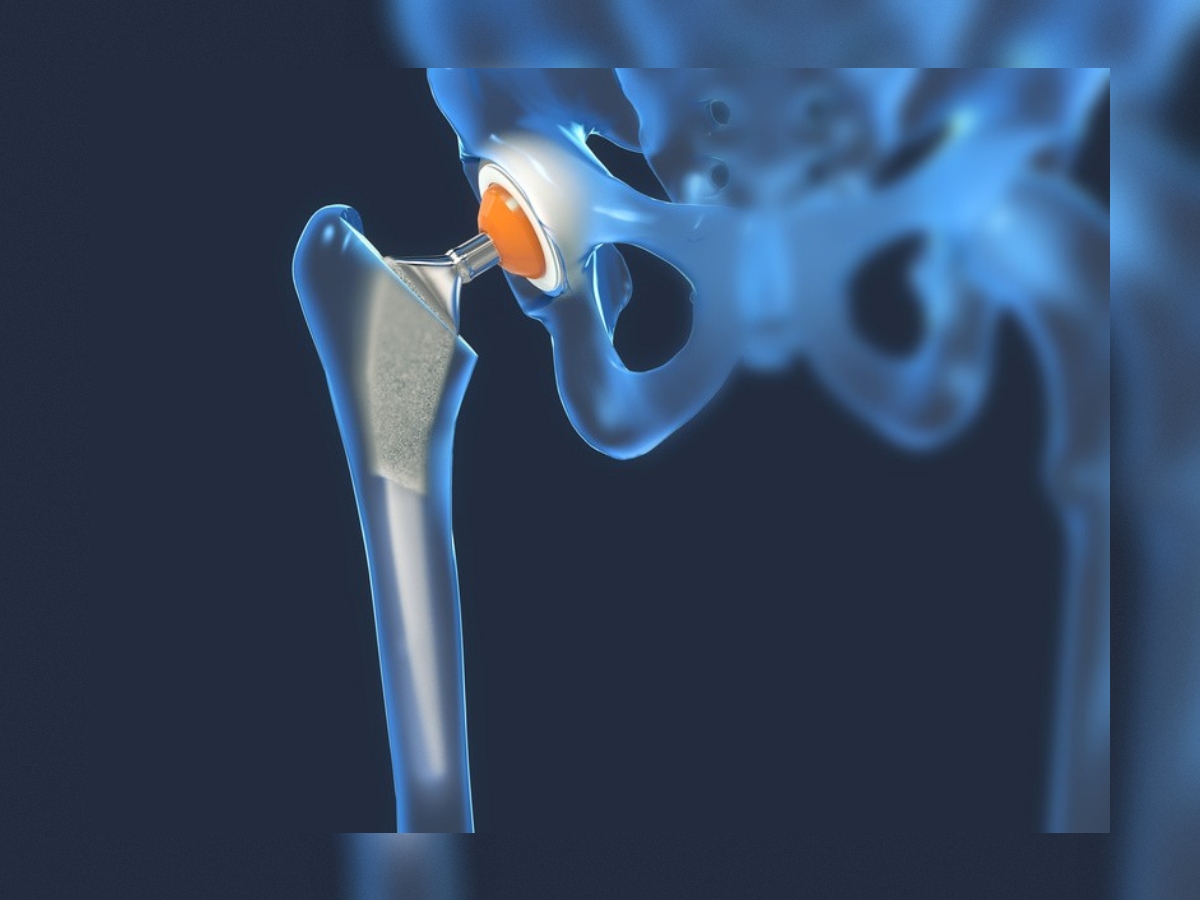

Prothèse de hanche

La prothèse de hanche (PTH) est une intervention chirurgicale qui remplace l'articulation coxo-fémorale usée ou endommagée par un implant, permettant de soulager la douleur et de retrouver une mobilité normale. Cette chirurgie est réalisée en cas d'arthrose sévère, de nécrose avasculaire ou de fracture du col du fémur.

- Prothèse totale de hanche (PTH): remplacement complet de la tête fémorale et du cotyle